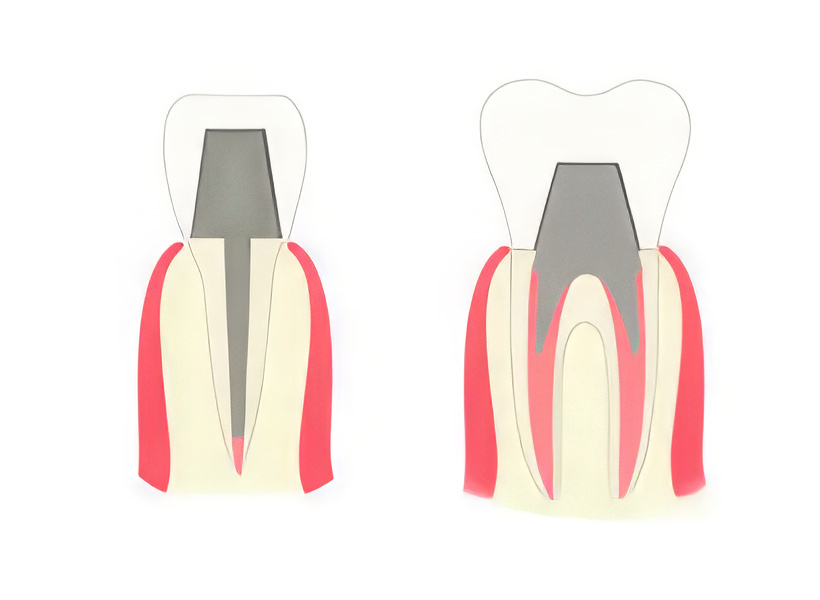

Культя зуба это

Культя зуба это 106 фото